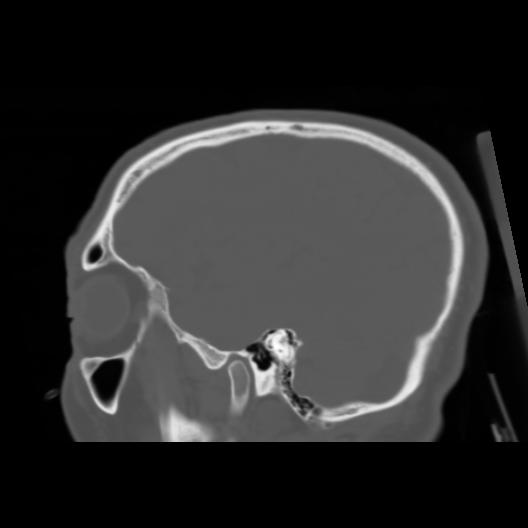

6 CEREBRO,,Sagittal,3.000,CEREBRO,Sagittal,